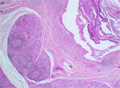

- (1)Sialolithiasis

Macroscopic findings:Yellowish-white stones (sialoliths) are observed within the salivary gland duct, accompanied by marked ductal dilatation.